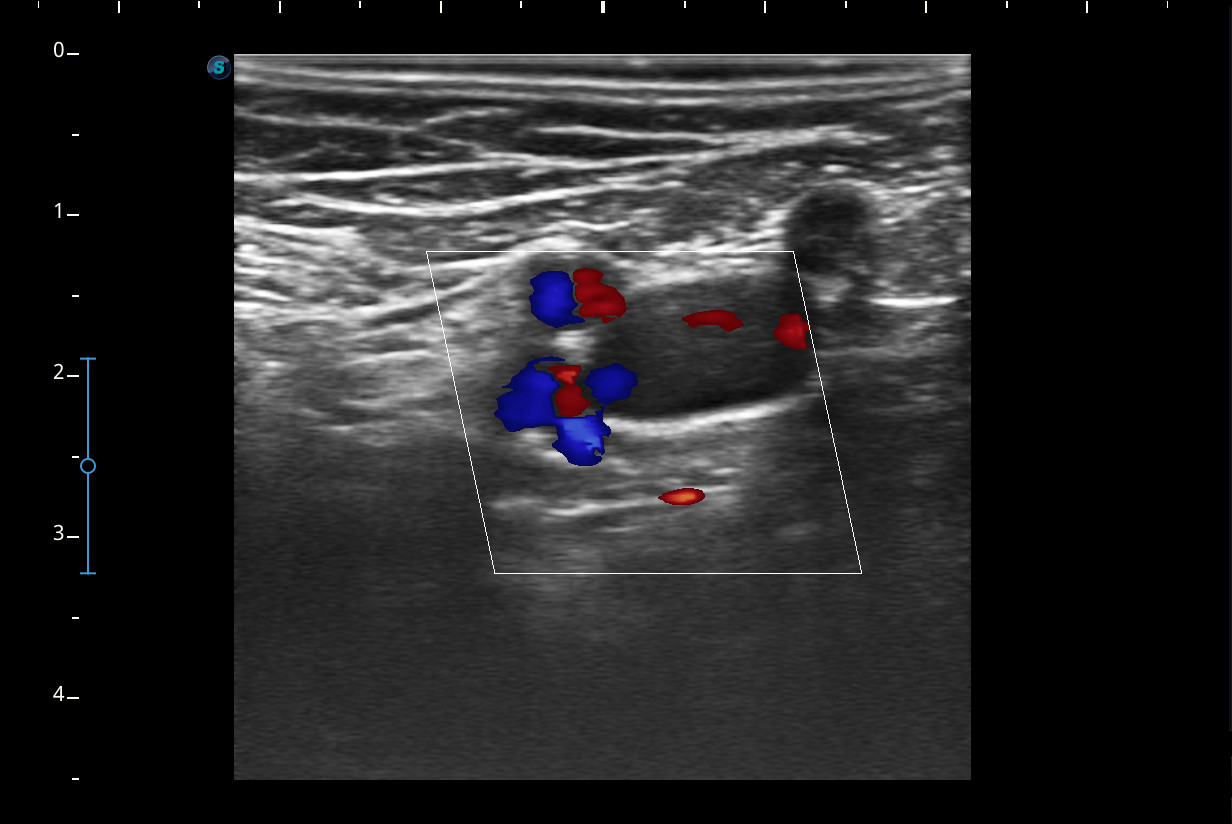

Se realiza ecografía del Miembro inferior derecho.

A nivel del hueco poplíteo se visualiza presencia de trombosis de la vena poplítea, no así en localizaciones proximales.